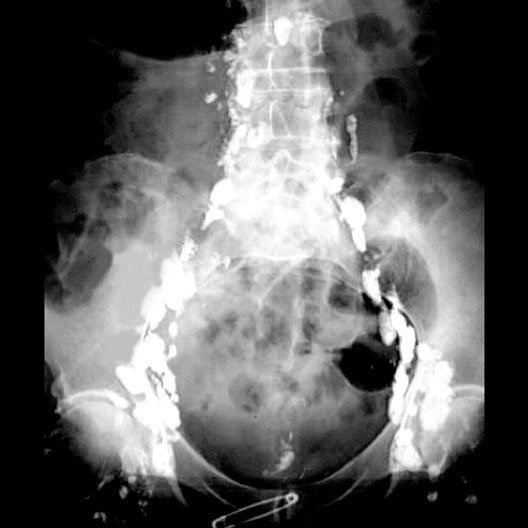

Lymphangiogram

1. Lumbar lymph nodes

2. Iliac lymph nodes